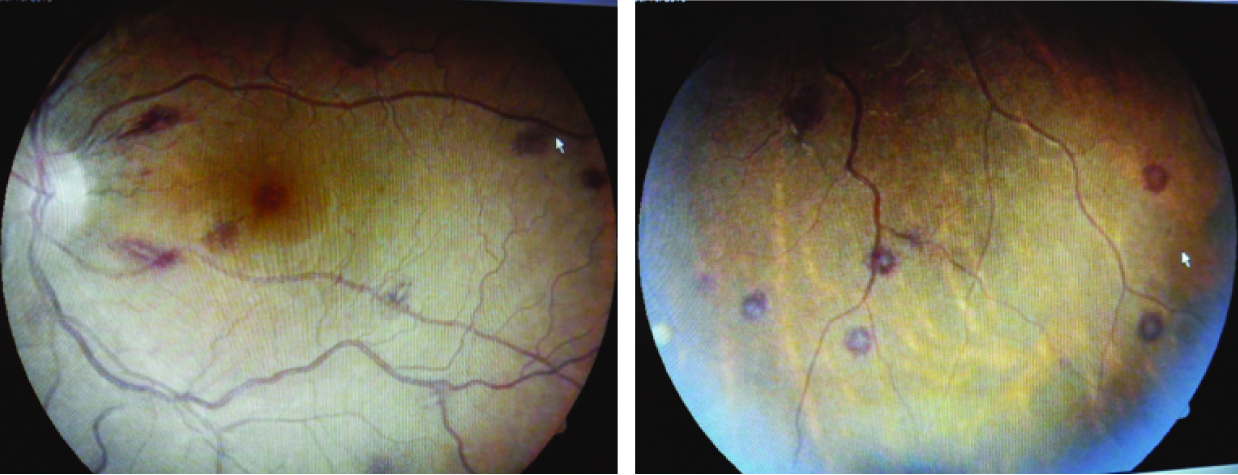

Two days after admission in the hospital he had history of sudden painless decrease in the vision from both eyes. His visual acuity in left eye was 6/9 and 9/12 in right eye. External ocular muscle movements were normal. Both pupils were round, equal, regular and reacting to direct and consensual light stimulus. Fundus examination revealed multiple retinal hemorrhages with white center and roth spots in all quadrants of fundus of both eyes. Retinal vessels were found tortuous. Papilledema, retinal whitening and exudates were absent [Table/Fig-1,2].

Retinal hemorrhages are frequently observed in Plasmodium falciparum infection, particularly with cerebral malaria in children but uncommon in non-cerebral malaria [2]. Malarial retinopathy includes various retinal changes and retinal signs in patients suffering from malaria. It includes retinal whitening, vessel changes, retinal hemorrhages and papilloedema. Retinal hemorrhages are very rare in Plasmodium vivax infestation [3–5]. The visual defects are usually reversible with complete recovery after treatment but rarely may be irreversible [6].

Malarial retinopathy is predominantly found in patients suffering from Plasmodium falciparum infestation with cerebral malaria in children but it can also be found in other form of malaria. Malarial retinopathy has also been found in adults with severe malaria and rare in Plasmodium vivax infestation [7]. It is characterized by retinal whitening (macular or perimacular), vessel changes (white or orange), retinal hemorrhage (particularly with white centres) and papilledema. Among these four changes, retinal whitening and vessel changes are specific and diagnostic of severe malarial disease [8]. The incidence of retinal haemorrhages was found in 46% cases of cerebral malaria [9]. This incidence was around 60% in children with cerebral malaria and was lower in less severe malarial disease [2].

Retinal hemorrhages in these patients usually absorbed spontaneously over the period of one to four weeks without retinal sequelae [9] and visual defect improved completely after successful treatment of malaria. Few cases have been reported with irreversible visual defects [7]. Our patient had peripheral parasitemia, severe anaemia, thrombocytopenia, hepatic dysfunction, mild renal dysfunction, raised CRP level and multiple retinal hemorrhages with white center. After successful treatment of malaria, he gained normal vision with normal visual acuity after one month. Thus we assume that severe vivax disease was responsible for retinal hemorrhages.